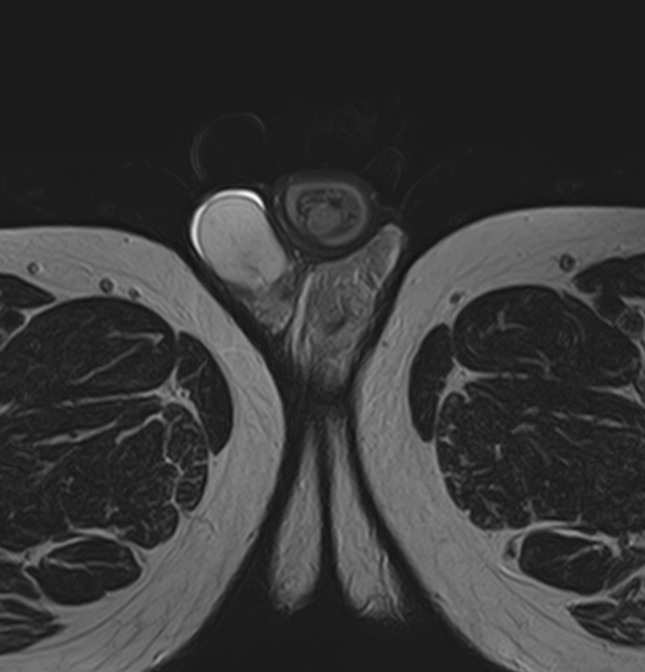

Метод позволяет диагностировать патологию мужских половых желез (яичек), их придатков и семявыносящих протоков. Эти органы, вместе с кровеносными сосудами, лимфатическими протоками и нервами, располагаются в мошонке – мешотчатом образовании из гладких мышц и кожи.

Во время исследования производится послойное сканирование в трех взаимно перпендикулярных плоскостях с шагом от 1 мм, в дальнейшем с помощью инновационных приложений аппарат трансформирует полученные данные в трехмерные изображения. Методика позволяет выявлять структурные изменения органов мошонки на самой начальной стадии. Особенно это важно для диагностики опухолей.

При подозрении на развитие объемных образований, для проведения дифференциальной диагностики, может применяться контрастное усиление. В таких случаях, пациенту внутривенно вводится контрастный препарат, содержащий гадодиамид (соли металла гадолиния), который способен «высвечивать» патологические очаги при попадании в зону действия магнитного поля томографа. С помощью контрастирования удается выявлять опухоли размером от 1 мм. Ранняя диагностика онкозаболеваний позволяет вовремя назначить необходимое лечение.

После того, как исследование окончено, задачей врача является расшифровка полученных снимков. Чаще всего удается определить следующие патологические процессы:

• Аномалии строения органа;

• Злокачественные или доброкачественные новообразования;

• Фиброзные изменения кавернозных тел;

• Сосудистые патологии, в том числе варикоцеле;

• Водянка яичка;

• Наличие абсцесса;

• Пневматоз;

• Склероз яичек;

• Крипторхизм;

• Воспалительные процессы;

• Аденомиоз;